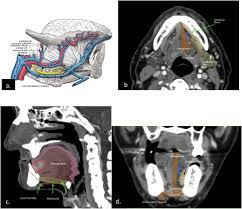

Mouth cancer starts in the cells lining the mouth. Moreover, the discoloring of the lining of the mouth may also be a sign of cancer. Cancer that arises from the jaw bone is termed primary jaw cancer. Although many jaw growths are benign, they can still do plenty of harm. Often, by the time a patient sees a doctor for a diagnosis, the tumor has grown into the neck. Gingiva cancer (also known as squamous cell carcinoma) is a progressive, rapid (weeks) local invasion of neoplastic epithelial cells within the oral cavity of dogs. Other conditions, like osteoporosis or arthritis, may also cause bone or joint pain. Although it's located in the front part of the mouth, it's actually considered a cancer of the head and neck. A canker sore looks like an ulcer, usually with a depression in the center. If a tumor spreads to the bone, it's called bone metastasis. A sore throat or persistent feeling that something is caught in the throat. This is known as a smoker's patch. Sneezing, difficulties in breathing, nose bleeds or other nasal discharges are common symptoms.

Picture of squamous cell carcinoma of the cheek Some of the signs are similar, including bleeding gums. Symptoms are similar to more typical osteosarcomas except that they may occur in very young children and are more widespread. Bone pain can cause a dull or deep ache in a bone or bone region (e.g., back, pelvis, legs, ribs, arms). It often causes changes in patches of skin, such as thick growths. Out of the various types of cancer, one is bone cancer which affects the. While a lump could be an infection or benign growth, these lumps could also be a sign that cancer is developing on the jawbone beneath the mouth's soft tissues. Some of the most common oral cancer symptoms and signs include: Cancer of the floor of mouth often looks like an ulcer and is painless. If a tumor near the jaw is hard to move when the doctor examines it, it often means that the cancer has grown into the jaw bone. A biopsy is the only way. Mouth cancer on your gums can sometimes be mistaken for gingivitis, a common gum inflammation. This aggressive type of cancer is more likely to spread to the lymph nodes

Taken by mouth or injection, they attack any cancer cells in the body. If the jaw bone looks normal on imaging tests and there's no evidence the cancer has spread there, the bone may not need to be cut all the way through. Jaw cancer results in pain in the area with difficulty in opening the mouth. Bone cancer is rare, making up less than 1 percent of all cancers. Lumps, swellings, fractures, joint tenderness and pain are some common symptoms of bone cancer in ankle and foot.

If a tumor near the jaw is hard to move when the doctor examines it, it often means that the cancer has grown into the jaw bone. Lumps, swellings, fractures, joint tenderness and pain are some common symptoms of bone cancer in ankle and foot. Bone pain can cause a dull or deep ache in a bone or bone region (e.g., back, pelvis, legs, ribs, arms). Other conditions, like osteoporosis or arthritis, may also cause bone or joint pain. A canker sore looks like an ulcer, usually with a depression in the center. As the cancer develops, though, the pain may become more persistent. Most cancer of the palate is squamous cell. The following are some mouth cancer pictures that can help you in knowing what does mouth cancer look like. Major signs that indicate bone cancer in foot and ankle. Leukoplakia (white and hardened patches) squamous cells is the name given to the flat cells that are present on the surface of the tongue, mouth and lips. If the jaw bone looks normal on imaging tests and there's no evidence the cancer has spread there, the bone may not need to be cut all the way through. This spread is called metastasis. Cancer that has started in one place can spread to and invade other parts of the body.